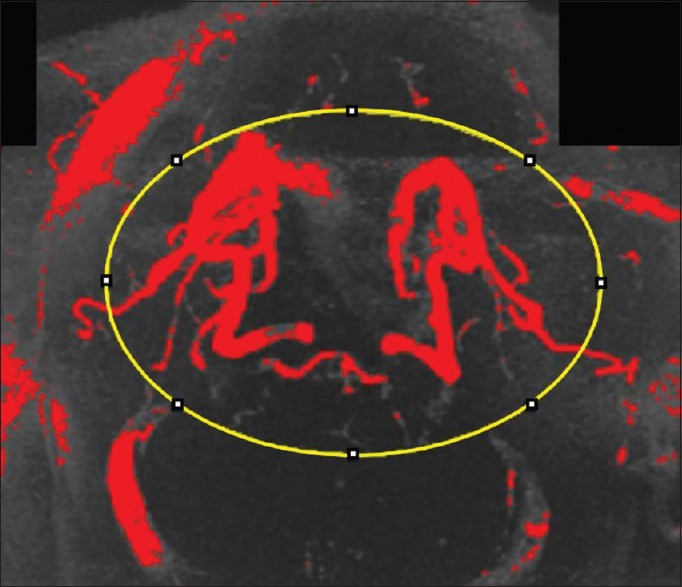

There are studies showing decreased blood flow in arteries that feed the brain when the neck starts to straighten and flexion of the neck affecting the air flow in babies! (5, 6) Pictures of the blood flow in the brain are shown below. This study showed improved brain circulation in a MRA by applying a Cervical Dennerol (orthotic device that induces curve in the neck)! (7)

“Our findings demonstrate preliminary evidence that loss of cervical lordosis may play a role in the development of changes related to the circle of Willis and cerebral artery hemodynamics and decreased blood flow in the brain.” (7)

- Katz EA, Katz SB, Fedorchuk CA, Lightstone DF, Banach CJ, Podoll JD. Increase in cerebral blood flow indicated by increased cerebral arterial area and pixel intensity on brain magnetic resonance angiogram following correction of cervical lordosis. Brain Circ. 2019;5(1):19‐26. doi:10.4103/bc.bc_25_18